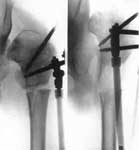

1.Врожденный вывих левого бедра.

2.Операция Шанца-Илизарова с одновременным удлинением бедра.

3.Демонтаж аппарата Илизарова.

4.Результат лечения.